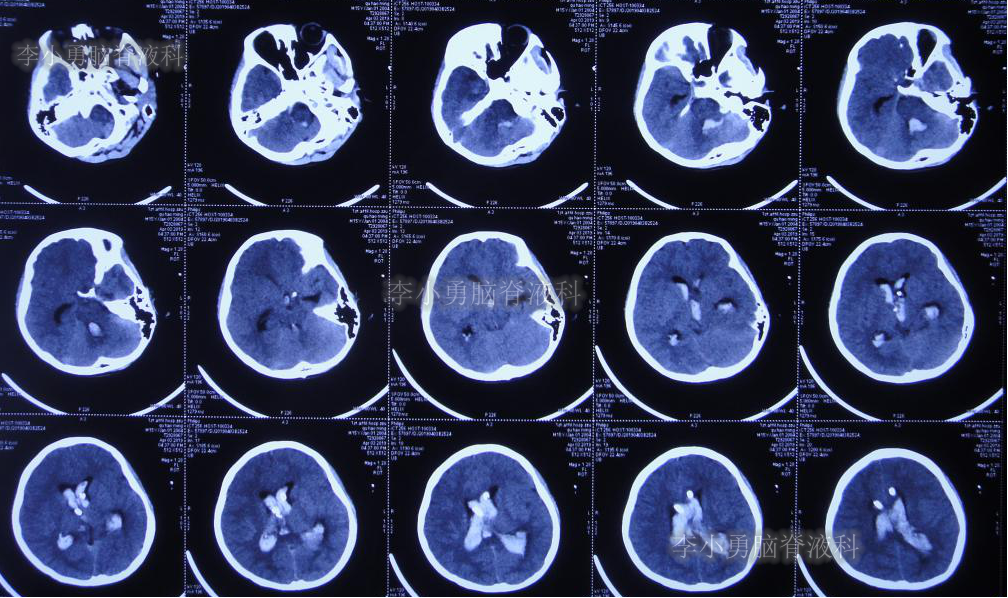

左侧颞角引流术后20天即2019年7月17日,复查头颅CT(图-21):左侧颞角积水消失,水肿消退;患者记忆力也逐渐好转。

图-21:2019年7月17日头颅CT:左侧颞角积水消失,水肿消退

左侧颞角引流术后33天即2019年8月1日,给予试夹闭右侧脑室外引流管,闭管前复查头颅CT(图-22)。

图-22:2019年8月1日夹闭前复查头颅CT

闭管40天后即2019年9月9日复查头颅CT(图-23):脑室仍无扩大。给予拔除右侧脑室外引流管并行左侧颞角-腹腔分流术。

图-23:2019年9月9日头颅CT:拔除右侧脑室外引流管后复查

出院后2个月即2019年12月9日,复查头颅CT示脑室系统较出院时无明显变化(图-25);但患者记忆力仍差。

图-25:2019年12月9日头颅CT

出院后9个月即2020年7月6日,再次复查头颅CT(图-26):未见异常。家属叙述:肢体活动正常,记忆力较前有些改善但较同龄人仍差,已重返校园(图-27)。

图-26:2020年7月6日头颅CT:未见异常